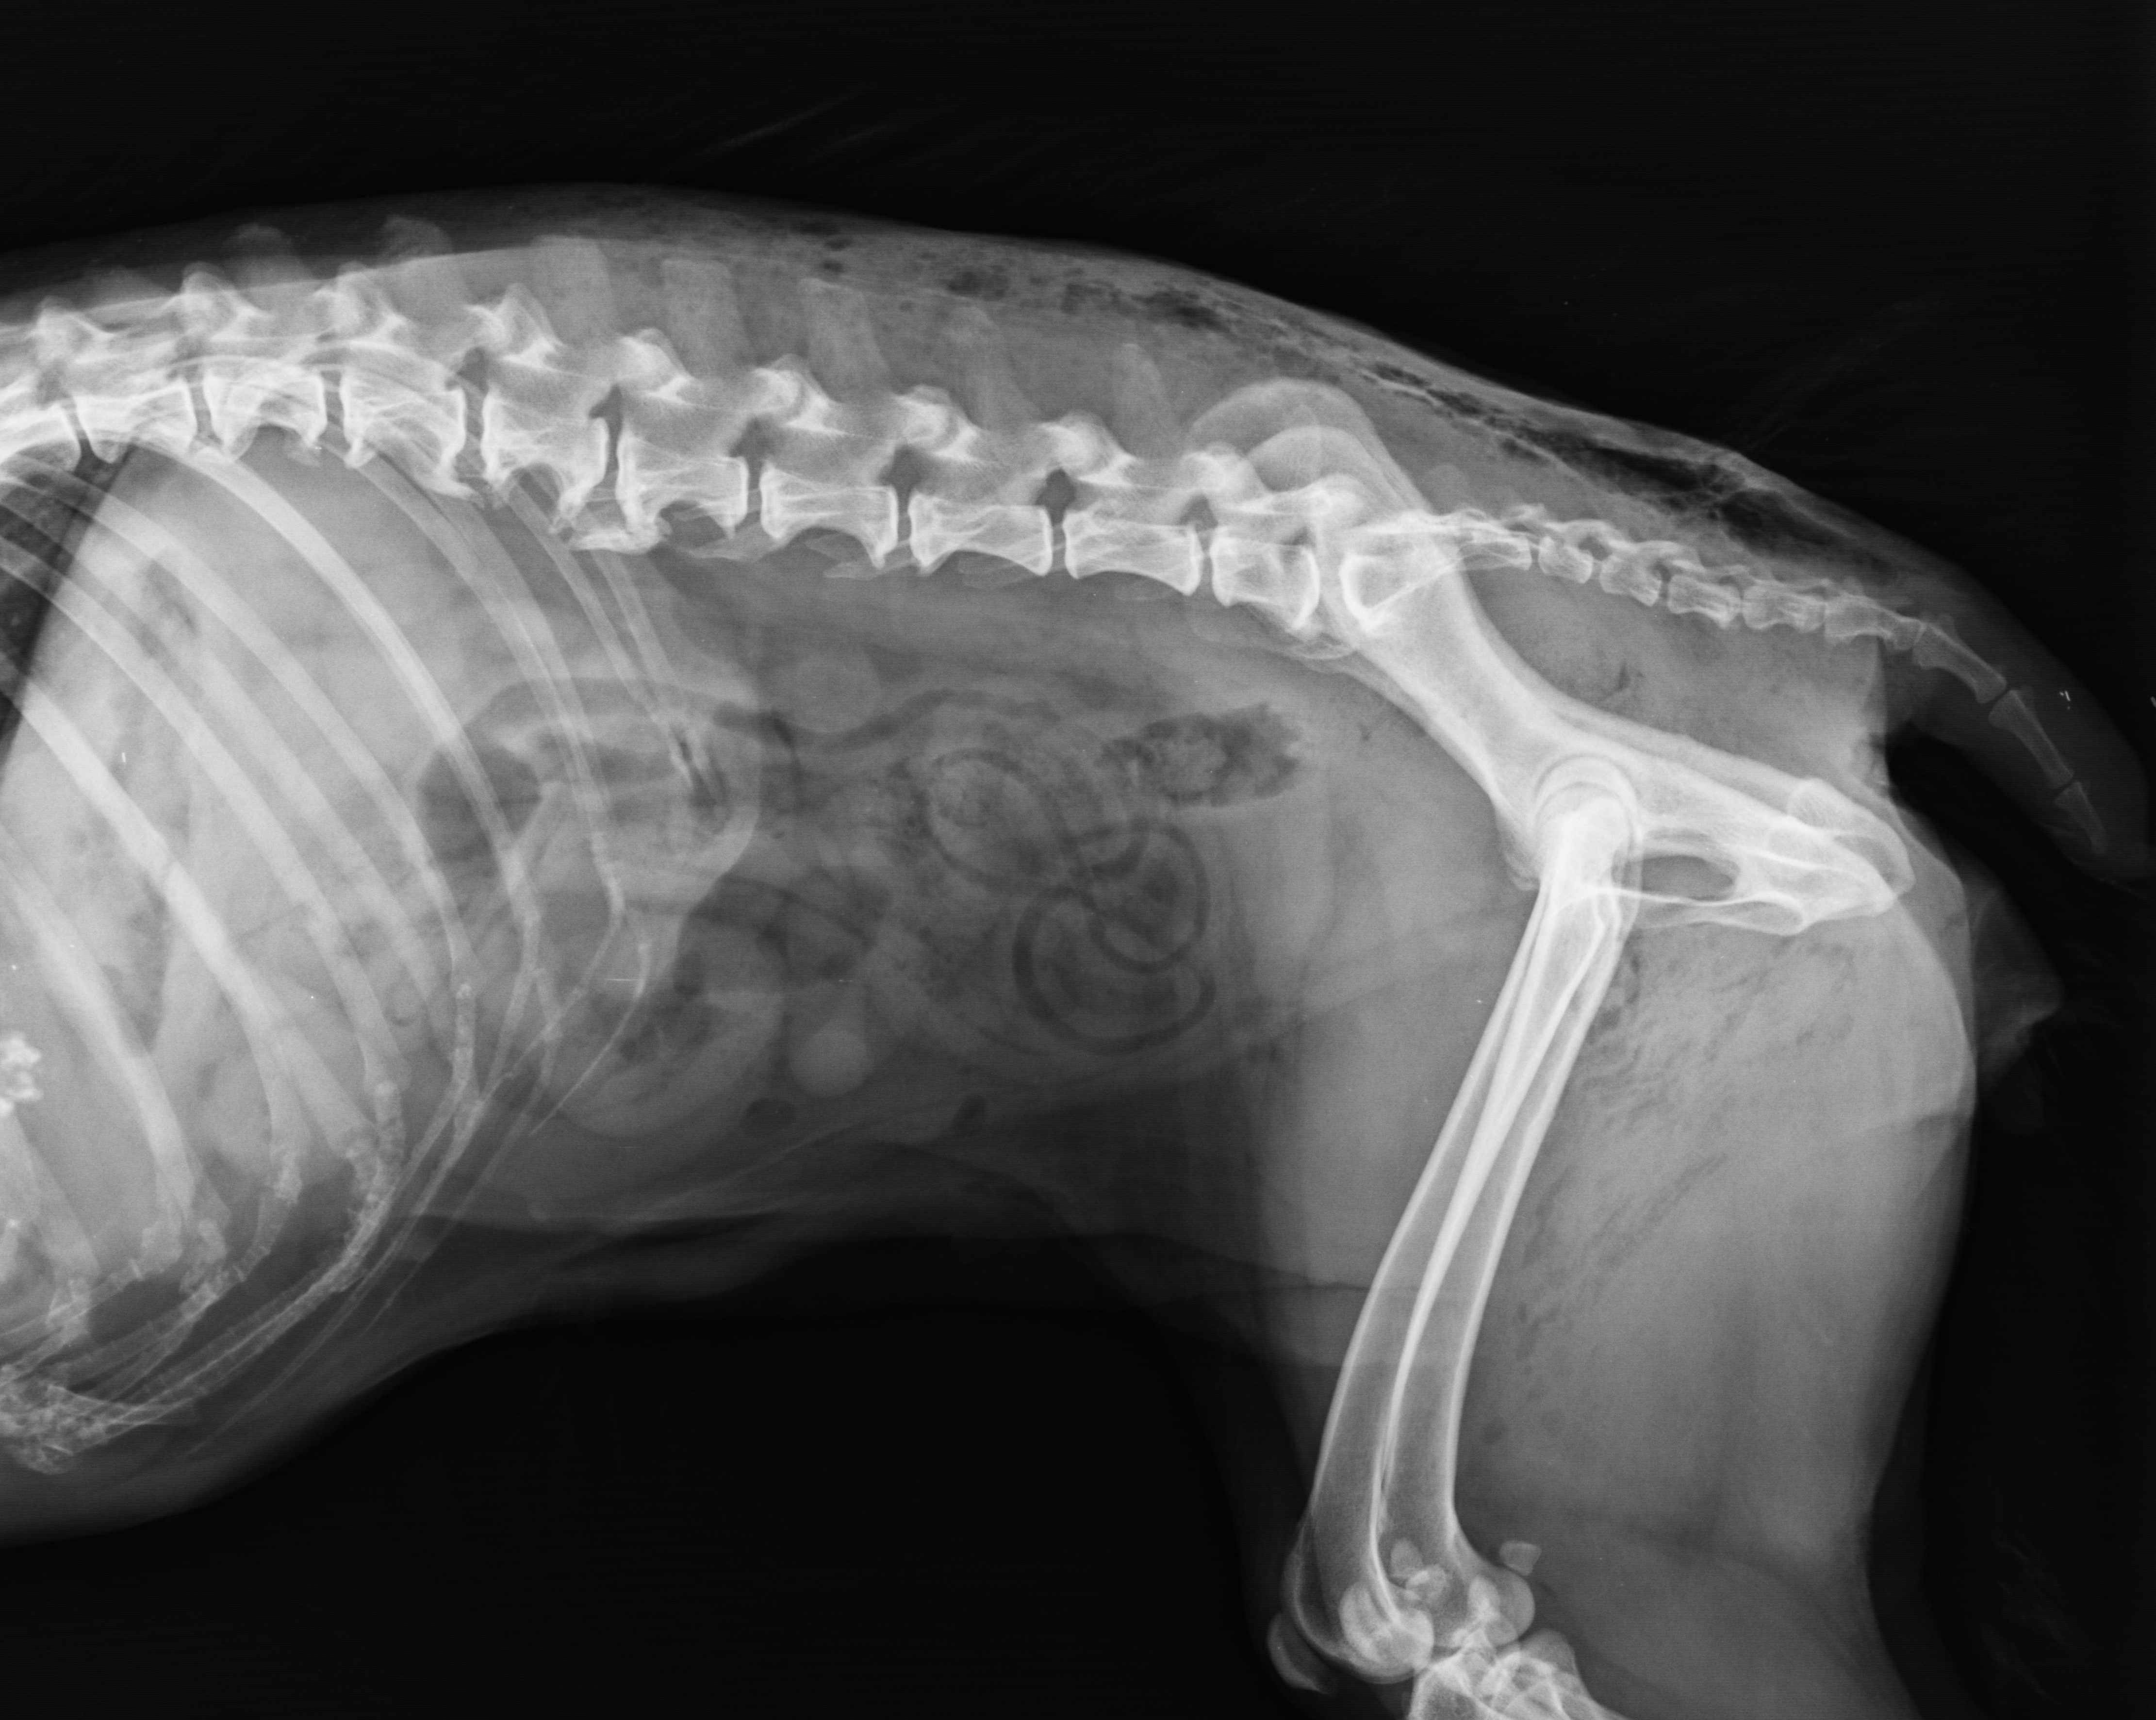

Arthritis Pain Management Strategies: Physical Medicine, Rehabilitation Exercises And What Owners Can Do At Home; Shockwave Therapy - Mechanisms And Practical Applications